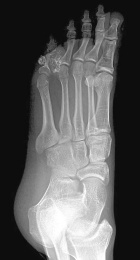

30 year old male with a five year history of a dull ache and mass in the left fifth toe

Zoom image: Radiological image Radiological image.